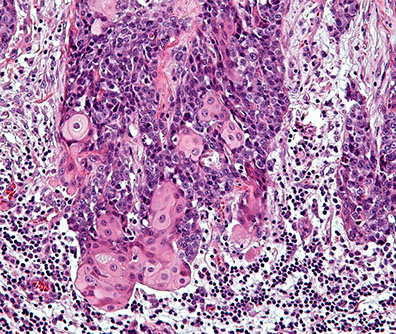

NUT midline carcinoma

NUT Midline Translocation Carcinoma

Rare, Small round blue cell tumor c abrupt transition to squamous epithelium

IHC: (+) CK, EMA, CD34 (var), p63, NUT

- neg: CD56, SYN, CHR, EBV,

Genes: NUT translocation confirms dx (BRD-NUT)

Px: very aggressive (~10 mo survival)